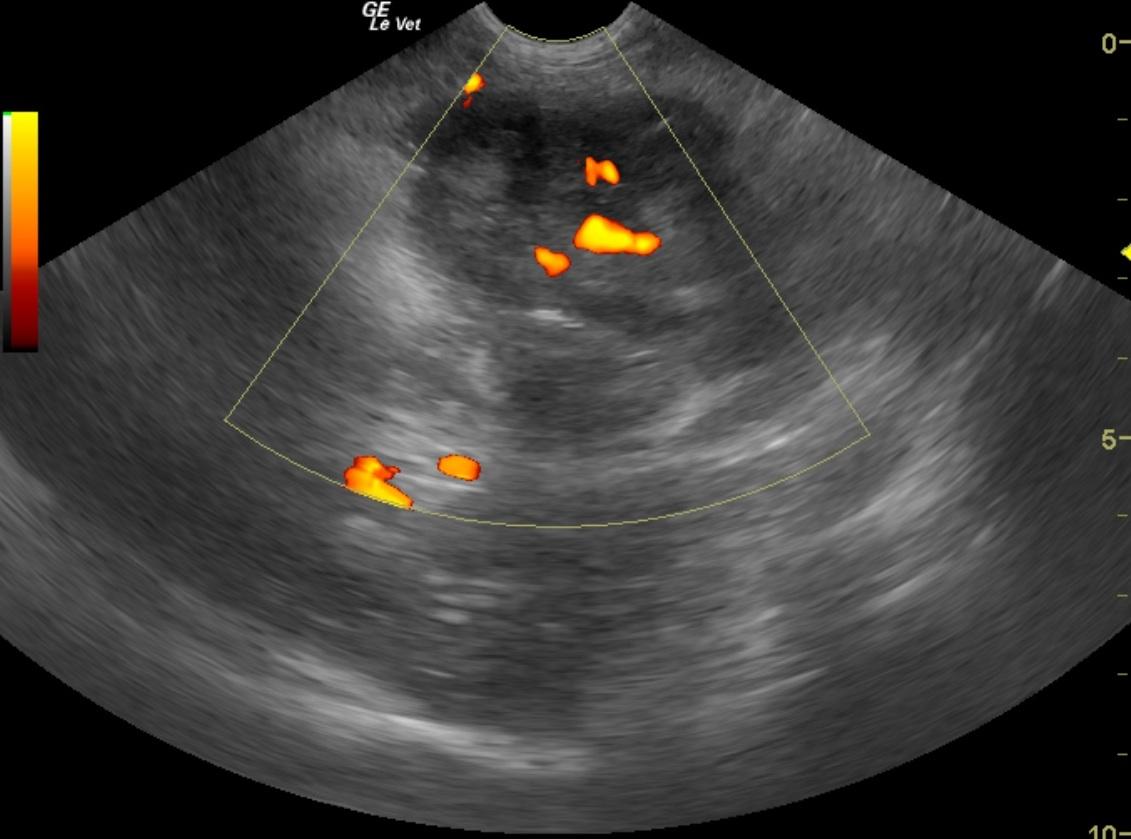

From members.sonopath.com

Intestinal stromal tumor in a 11 year old MN Brittany Spaniel dog Members Dog Gastrointestinal Stromal Tumor gastrointestinal stromal tumor (gist) is a malignant mesenchymal neoplasm described in humans, dogs, and. fifty canine gastrointestinal (gi) mesenchymal tumors were examined to determine the occurrence of leiomyomas. gastrointestinal stromal tumors (gists), leiomyomas, and leiomyosarcomas are common mesenchymal neoplasms in the. fifty canine gastrointestinal (gi) mesenchymal tumors were examined to determine the occurrence of leiomyomas. . Dog Gastrointestinal Stromal Tumor.

Intestinal stromal tumor in a 11 year old MN Brittany Spaniel dog Members Dog Gastrointestinal Stromal Tumor fifty canine gastrointestinal (gi) mesenchymal tumors were examined to determine the occurrence of leiomyomas. fifty canine gastrointestinal (gi) mesenchymal tumors were examined to determine the occurrence of leiomyomas. adenocarcinoma, leiomyosarcoma, and lymphoma are the most common canine intestinal tumors. gastrointestinal stromal tumor (gist) is a malignant mesenchymal neoplasm described in humans, dogs, and. in dogs,. Dog Gastrointestinal Stromal Tumor.